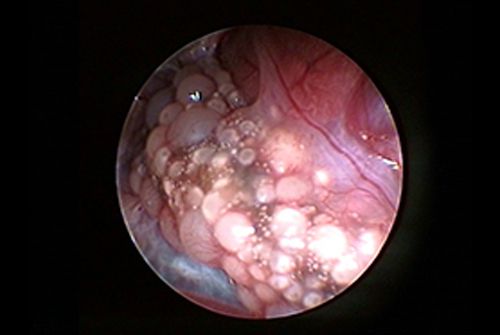

• Weiblicher Vogel

Beim weiblichen Vogel erkennt man das auf der linken Körperseite liegende Ovar (Eierstock). Bei geschlechtreifen aber inaktiven Tieren ist die Oberfläche himbeerartig, bedingt durch die vielen rundlichen Follikel. Bei eintretender geschlechtlicher Aktivität fangen vereinzelte Follikel an zu wachsen und werden im Laufe der Eibildung anschließend zur Ovulation zum Eidotter. Siehe hierzu auch unseren Bericht über die Bildung des Vogeleis.